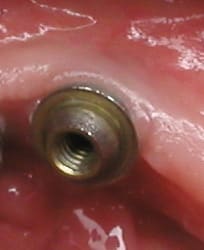

non, et pour plusieurs raisons: les spires du swissplus sont en reverse buttress et au niveau de la plateforme prothétique c'est un biseau à 45°

là les spires sont plutôt en buttress et c'est complètement plat sur la plateforme prothétique

il y a une pièce vissée dans l'implant pour transformer cette connexion interne en multiunit...et ce système, je ne l'avais encore jamais vu!

Il s'agirait finalement d'implants Tekka progress (?)